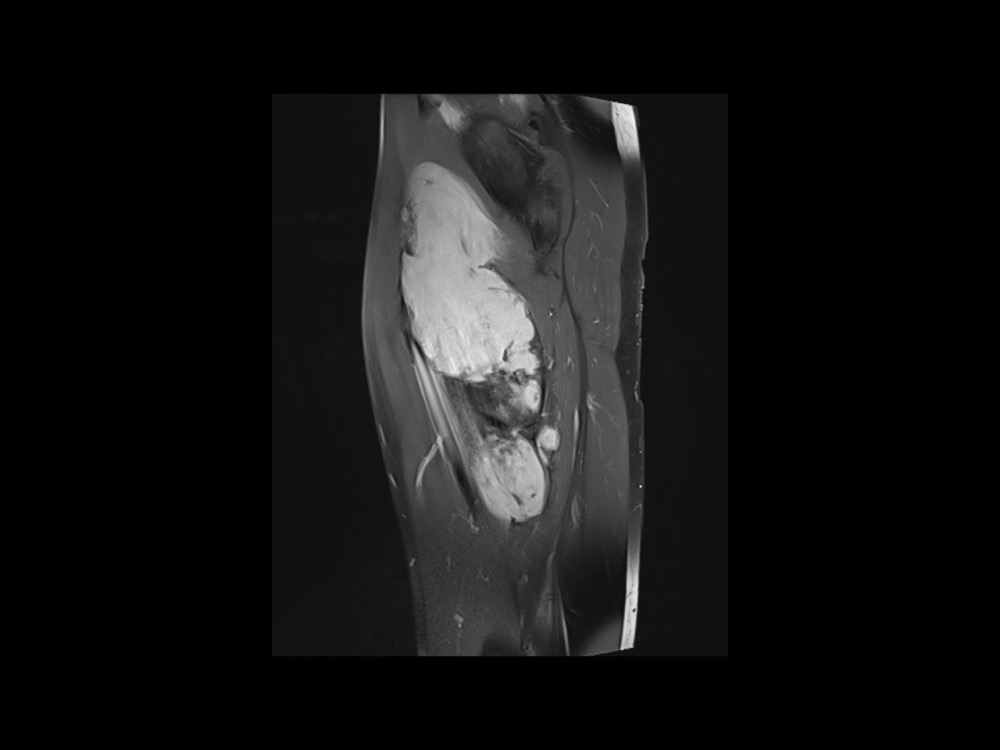

Moalla / Mihoubi-Bouvier / Drapé 18/05/2022